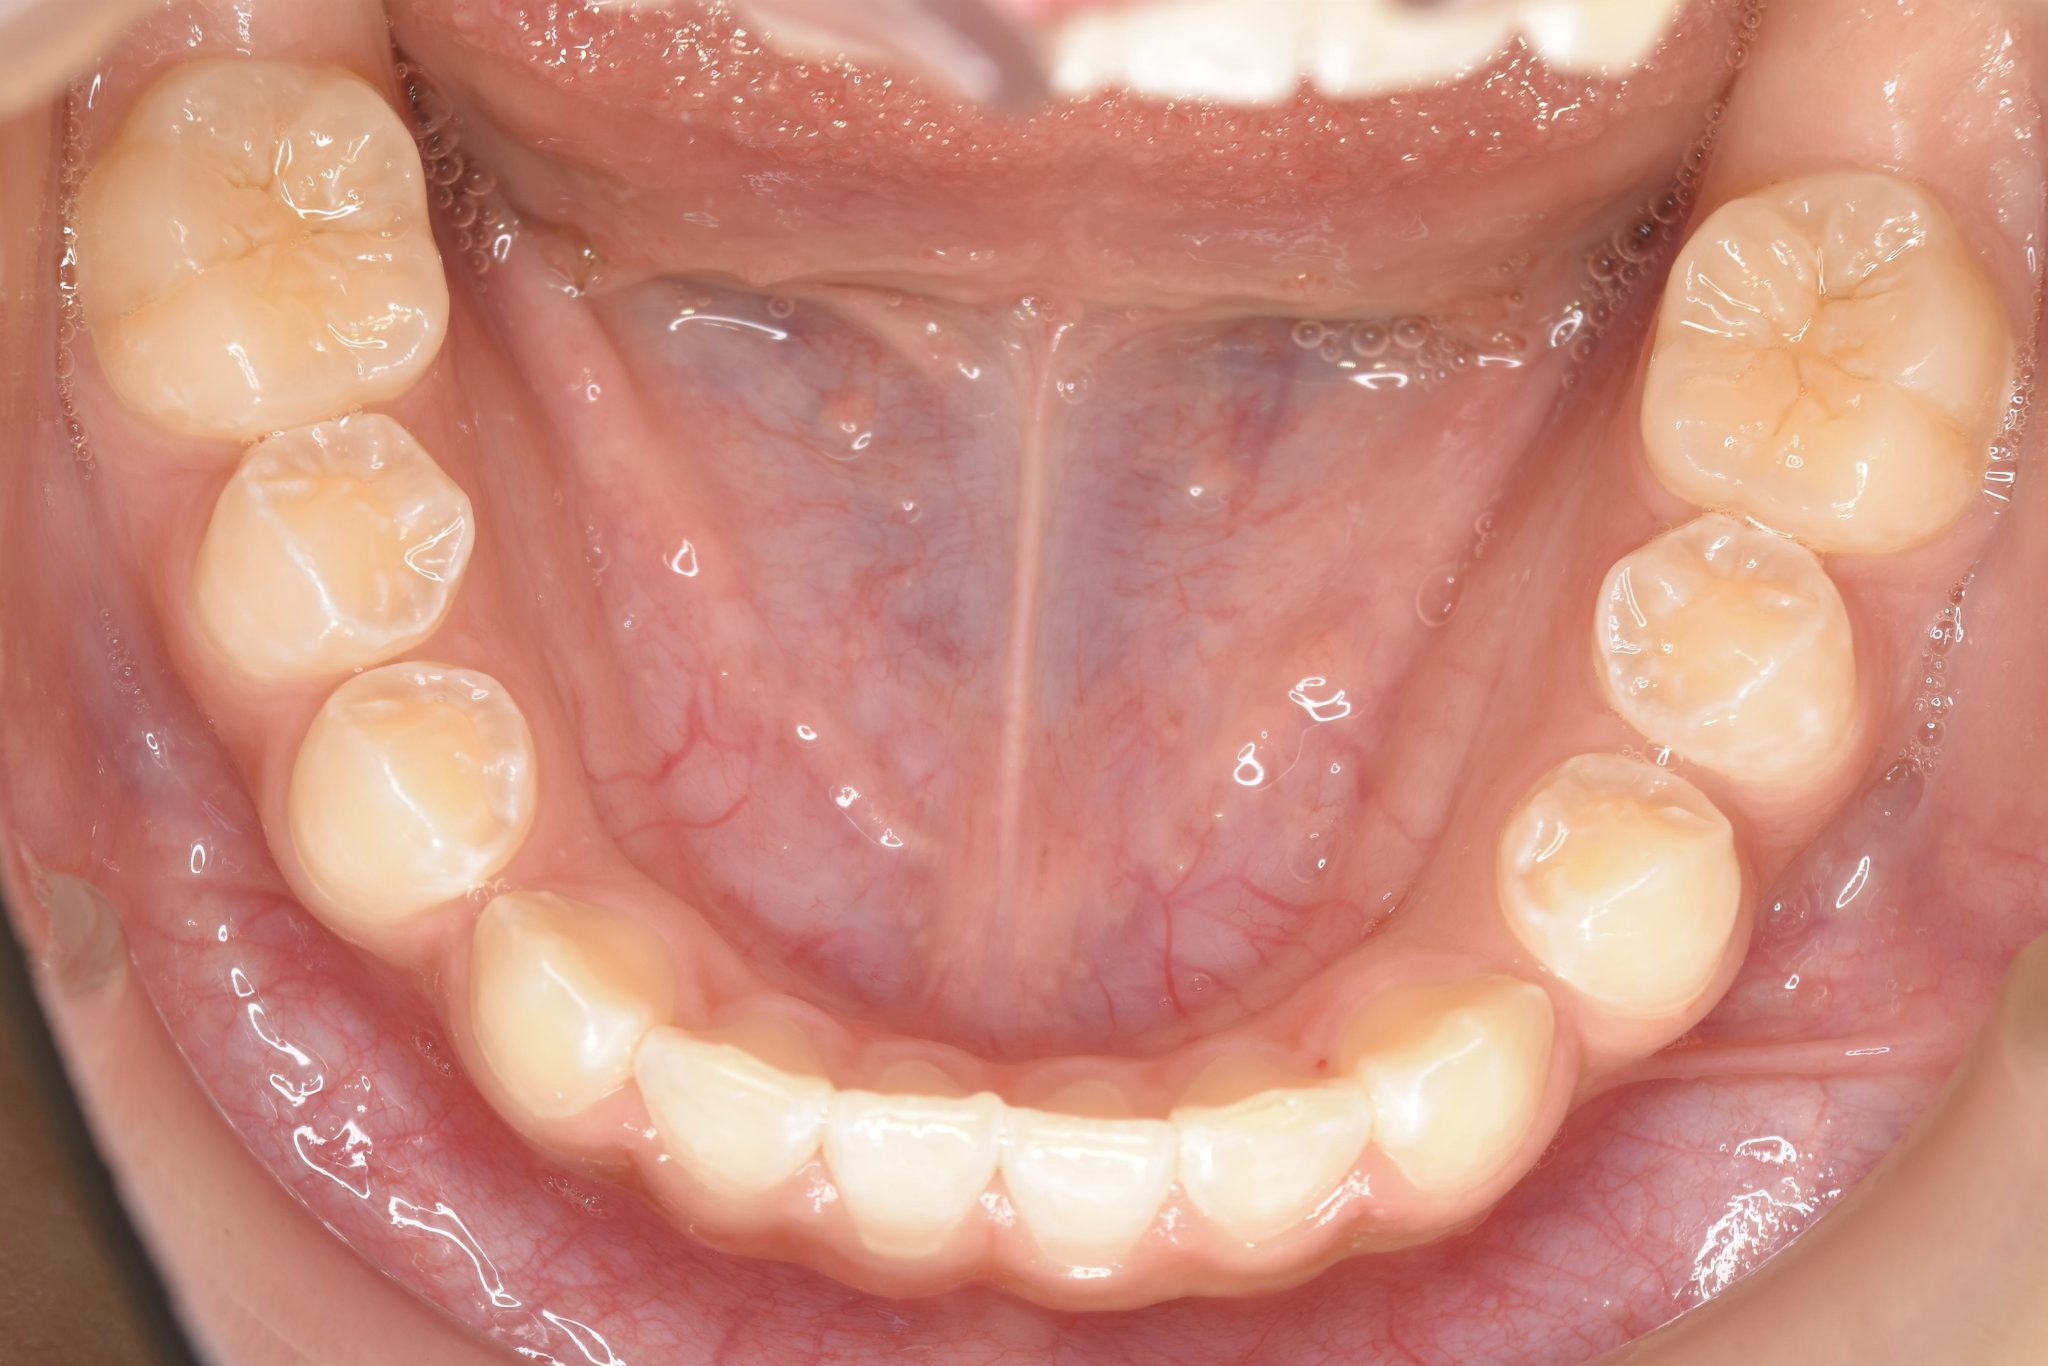

アフター

子どもの矯正治療|症例_858